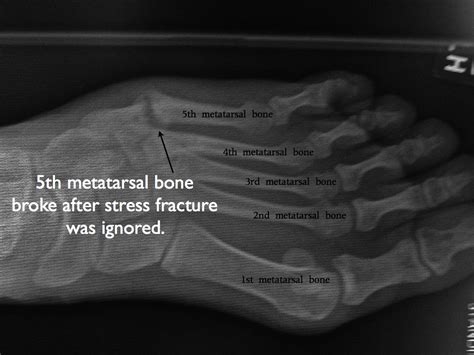

Stress Fracture Top Of Foot / Crossfit - My Foot - 4th Metatarsal Fracture - 9/22/15 ... - Here we explain the common causes of foot pain including…. 🦶the most common navicular fracture is a navicular stress fracture!🦶 this is a top of the foot stress fracture that can leading to radiating and aching pain. Track and field athletes and military recruits who carry heavy foot problems. So it's not a surprise that many people experience foot pain in some capacity. Midtarsal stress fractures it is important to note that stress fractures of the tarsal bones such as the navicular or cuboid bone can be much more difficult to the top arrow is the neck of the talus, usually the result of a sudden upward jarring of the foot as seen in car accidents, and the bottom arrow points. Stress fractures are often difficult to diagnose, as the breaks are very fine and often do not show up on initial.

Stress fractures can occur to any bone in our bodies, but our feet are the most common location. They're also comprised of ligaments and tendons, which carry the full weight of our bodies every day. People who have flat feet or high, rigid arches are more likely to develop stress fractures. They are most common in the second and third metatarsal bones. Our feet are more than just bone and muscle;

People who have flat feet or high, rigid arches are more likely to develop stress fractures. A stress fracture of the 2nd or 3rd metatarsal bone is sometimes called a 'march fracture' because soldiers running in boots often get it! It is caused by unusual or repeated stress,this is in contrast to other types of fractures, which are usually characterized by a solitary, severe impact. Here we explain the common causes of foot pain including… Stress fractures can become very serious if left untreated, so it is important to seek appropriate i have pain over the top of my toes and my foot is swollen.

Stress fractures are small breaks in the bones of the feet, legs, or hips due to pressure put on those areas. A stress fracture is one type of incomplete fracture in bones. Stress fractures are not typically sudden events, and they can begin as tiny cracks in the bone that gradually enlarge with repeated impact over time. This can occur anywhere on the foot but it is most likely to be seen on the top portion because of injury to a metatarsal. Here we explain the common causes of foot pain including…